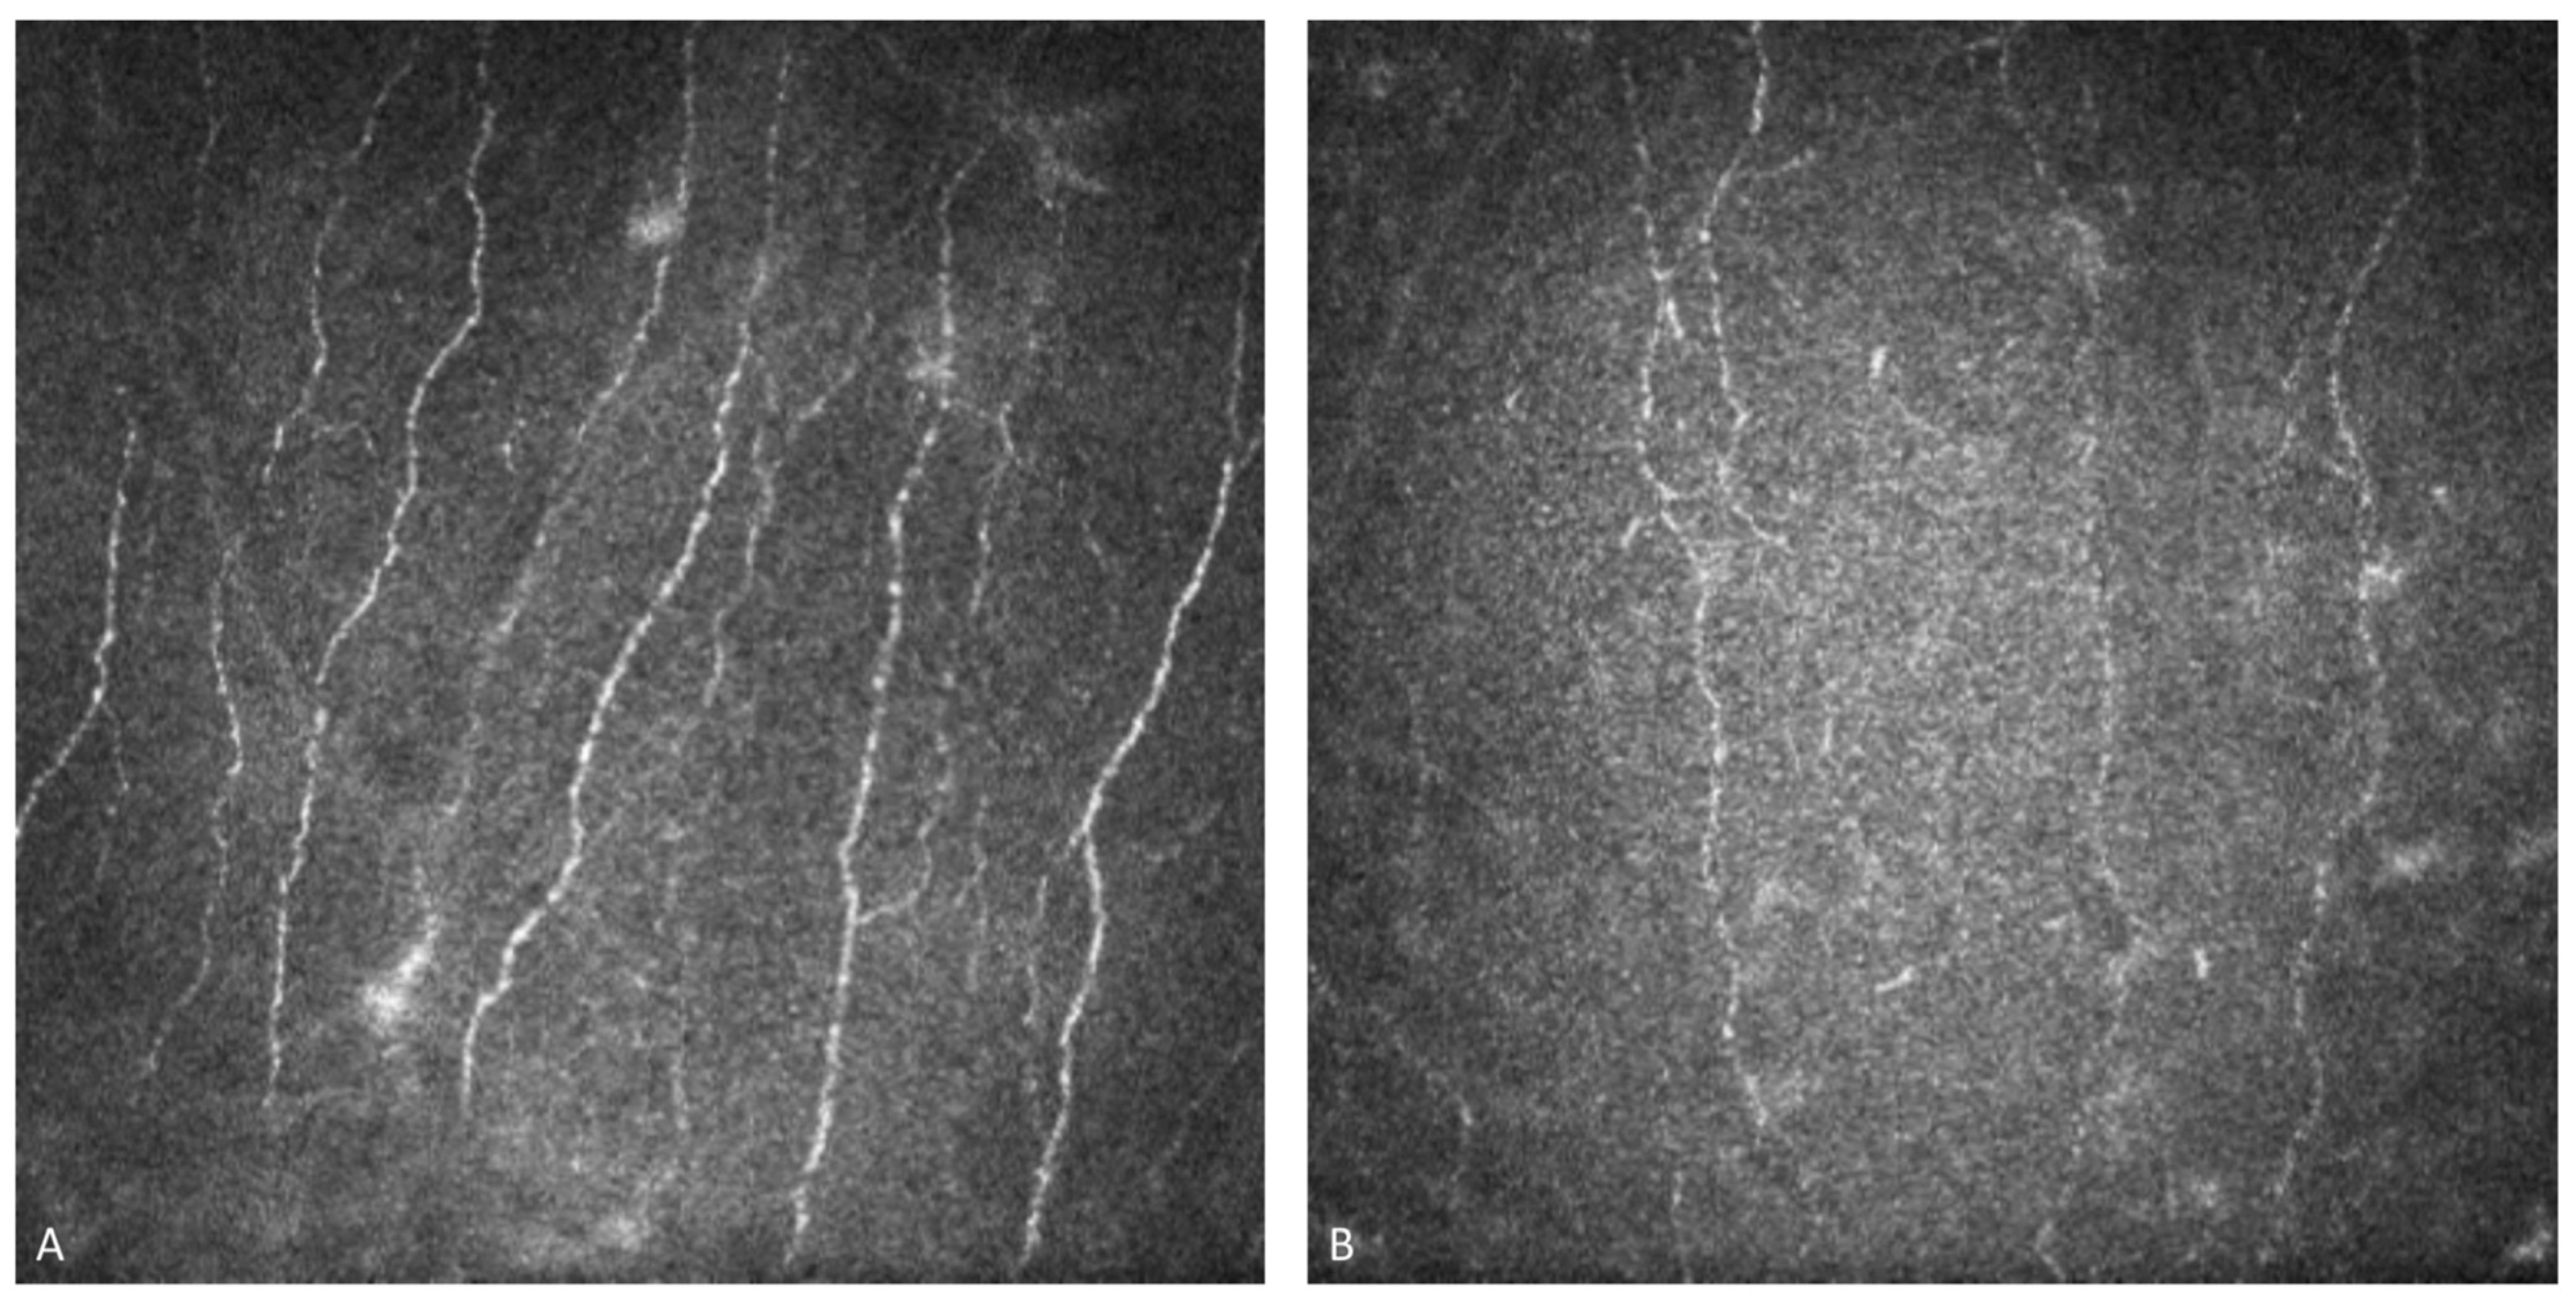

Figure 3. In vivo confocal microscopy examination of a healthy cornea (A) compared with a Fabry disease patient’s cornea (B), characterized by hyperreflective spots in the basal epithelium cells. The different appearance of corneal epithelial cells can help differentiate the etiology of cornea verticillata.

This distinctive sign has been recognized for over a century: following the first drawing of a corneal vortex pattern published in 1910 by Fleisher, in 1946, Gruber formally named the spiral pattern “cornea verticillata”. These inclusions fill the cells of the corneal basal epithelium layer and then spread to the basal membrane and extracellular spaces. The unmetabolized Gb-3 is stored in distended lysosomes, which can no longer function properly in intra- and extracellular transportation, leading to tissue dysfunction. In some cases, the lysosomal membrane fuses with the cellular membrane, releasing the Gb-3 load into the extracellular space. It is also possible that the lysosomal membrane fuses with other organelles, releasing Gb-3 into them. This storage results in hyperreflective microdots distributed in the basal epithelium, basal membrane, and sometimes in anterior stroma. The inclusions can appear in streaks, patches, or have a diffuse pattern. Gb-3 deposits can be detected by slit-lamp biomicroscopy examination or in vivo confocal microscopy, which has greater sensitivity in identifying the hyperreflective specks in the basal epithelium layer [39] Figure 3.

It is important to note that CV is not exclusive to FD. The primary cause of CV is the use of amphiphilic drugs, such as amiodarone. Differentiating between these two etiologies cannot be achieved by slit-lamp examination alone, but can be achieved by in vivo confocal microscopy (IVCM) [45,46]. This exam highlights differences between the two forms: in FD, the Gb-3 accumulation fills the entire cytoplasm with a regular pattern and homogeneous size, and the reflectivity is less pronounced compared to CV caused by amiodarone accumulation. Additionally, the subepithelial nerve plexus and endothelium are not affected by inclusions in FD [38,47].